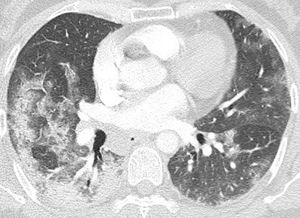

60-year-old white woman who was a former smoker. She presented to the hospital with a 5-day onset of low-grade fever, cough, dyspnea, and odynophagia; she had been using amoxicillin-clavulanate for the previous 4 days and tested positive for SARS-CoV-2 at admission. At the emergency department, she was started on cefepime later switched to meropenem due to clinical and laboratory deterioration. On admission, a CXR showed scarce bilateral opacities. Dexamethasone was started on day 1 of hospitalization, and CPAP was started on day 10 (when her P/F ratio on arterial blood gas was 61.6). Since her clinical status showed little improvement, she underwent a CT scan on day 14, exhibiting signs of OP (Fig. 2). Prednisone was started on the following day at 1 mg/kg PO, and in less than 48 h, she tolerated a tapering off of ventilatory support. She was discharged, breathing on room air, after four days of a high dose corticosteroid.